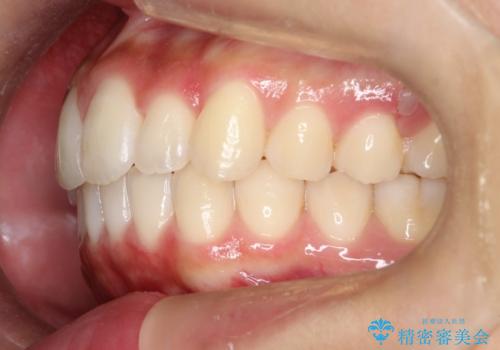

抜歯は行わず上顎の奥のスペースを利用して歯をスライドする方法の他に歯列弓の拡大やディスキング(歯と歯の間の隙間を作る処置)を行い叢生を改善しました。

歯の大きさの不揃いが原因の正中のズレは、ディスキング量を調整することで合わせています。

見た目、嚙み合わせ及び、治療期間や施術内容に大変ご満足いただきました。